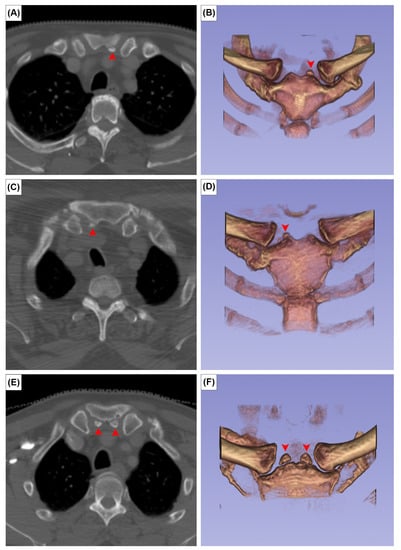

The prevalence of the six anatomical variations are presented in Table 1. Cohen’s ϰ value was 0.94 for all variants. However, after discussion and consultation with an expert radiologist, Cohen’s ϰ reached 1.00. The OA was observed in 20 patients, a crude prevalence of 3.3%. It was bilateral in 5 patients (25%) and unilateral in 15 (75%). Out of 1212 clavicles investigated, the true prevalence of OA was 1.9% (23 cases). The OA was classified as meso-acromion (Figure 1A) and pre-acromion (Figure 1B) in 19 (82.6%) and 4 (17.4%) acromia, respectively. The meta-acromion type was not observed.

Figure 1. Axial CT images showing two types of os acromiale: meso-acromion (A) and pre-acromion (B). Asterisks indicate the os acromiale.